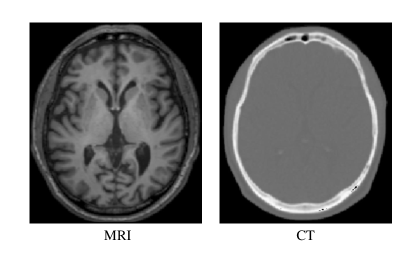

Refer to caption

Figure 1: A pair of corresponding brain MR (left) and CT (right) images from the same subject

It is technically difficult to directly estimate CT image from MR image. As shown in Fig. 1, CT and MR images have very different appearances. MR images contain much richer texture information than CT images. Therefore, it is challenging to directly estimate a mapping from MRI to CT.

• The brain dataset was acquired from 16 subjects with both MRI and CT scans in the Alzheimer’s Disease Neuroimaging Initiative (ADNI) database (see www.adni-info.org for details). The MR images were acquired using a Siemens Triotim scanner, with voxel size 1.2×1.2×1mm31.21.21superscriptmm31.2\times 1.2\times 1~{}\text{mm}^{3} , TE 2.95  ms, TR 2300  ms, and flip angle 9superscript99^{\circ}; The CT images, with voxel size 0.59×0.59×3mm30.590.593superscriptmm30.59\times 0.59\times 3~{}\text{mm}^{3}, were acquired on a Siemens Somatom scanner. A typical example of preprocessed CT and MR images is given in Fig. 1.